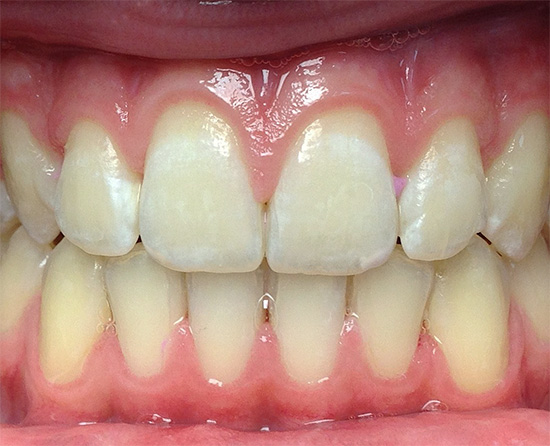

La carie viene mostrata nella prima fase di sviluppo quando si tratta di un punto bianco o gessoso (ecco come appaiono le aree dello smalto demineralizzato):

Nella foto: la carie in una fase iniziale di sviluppo:

Questo stadio di sviluppo della patologia è chiamato stadio del punto bianco: qui si verifica solo il danno iniziale allo smalto e la formazione di pori in esso sotto l'influenza di acidi aggressivi dalla cavità orale. Lo smalto perde la sua lucentezza, acquisisce un colore bianco più chiaro e saturo.

Ecco alcune altre foto di carie sul palco spot: